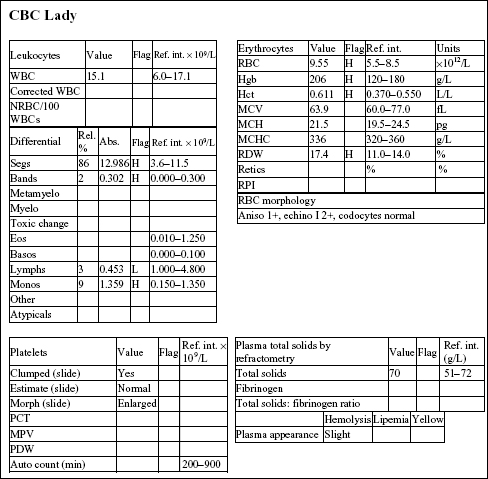

Lady, a 15-year-old F(s) Chihuahua X dog, had lethargy and a severe heart murmur.

The Hct, Hgb, and RBC count are all mildly increased, indicating erythrocytosis. Although the RDW is increased, this does not correlate with an increase in anisocytosis. The total solids are not increased. There is a mild neutrophilia, very mild left shift, lymphopenia, and mild monocytosis. The leukogram changes are consistent with stress (high levels of endogenous cortisol).

The chloride is decreased relative to the sodium, suggesting selective chloride loss, possibly from vomiting (not given in the history). There is a high anion gap metabolic acidosis, which may be due to decreased tissue perfusion. The mild azotemia (increased phosphorus, urea, and creatinine) is likely pre-renal from reduced renal perfusion, given the urine specific gravity (SG). Mild hyperglycemia and hypercholesterolemia are unlikely to be clinically significant. Mildly increased alkaline phosphatase (ALP) activity could be due to cholestasis or enzyme induction from chronic stress/elevated cortisol.

The urine SG indicates adequate renal function. Protein at 2+ could be significant; however, this could be better assessed by urine protein to creatinine ratio. Blood reaction appears to be due to mild hematuria. This is a free flow sample, so hematuria is unlikely to be iatrogenic (as seen with cystocentesis sampling), unless the bladder had been manually compressed to obtain the sample.

• The erythrocytosis is likely to be absolute and secondary to cardiac disease. EPO levels would be expected to be elevated because the erythrocytosis is a physiologic response to decreased arterial pO2 caused by heart failure.